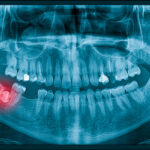

A pediatric dentist can conduct a thorough examination, potentially supplemented by X-rays, to ascertain the extent of the infection. Procedures like pulpectomies can salvage even severely decayed teeth if initiated promptly. Conversely, delays can lead to irreparable damage, necessitating tooth extraction.